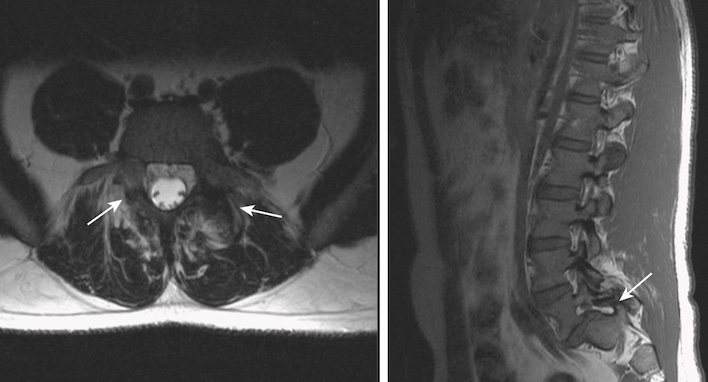

Chụp MRI

- Với trẻ em, chụp cộng hưởng từ (MRI) được xem là thăm dò hình ảnh đầu tiên, vì nó thể hiện mức độ thống nhất cao với SPECT / CT trong chẩn đoán hở eo ở trẻ vị thành niên mà không có nguy cơ chiếu xạ.

- Dấu hiệu: hình ảnh MRI đứng dọc với kỹ thuật bão hoà mỡ có thể xác định phù tủy xương biểu hiện phản ứng với stress ở phần eo trước khi gãy xương, và do đó trước khi có bất thường trên CT hoặc X quang.

- Khiếm khuyết gãy xương thường được ghi nhận là thiếu sự liên tục của xương giữa mỏm khớp trên và mỏm khớp dưới trên hình ảnh T1 đứng dọc (Hình 6).

- MRI cũng hữu ích để đánh giá đĩa đệm, phân độ trượt đốt sống và đánh giá lỗ thoát thần kinh cũng như sự chèn ép rễ.